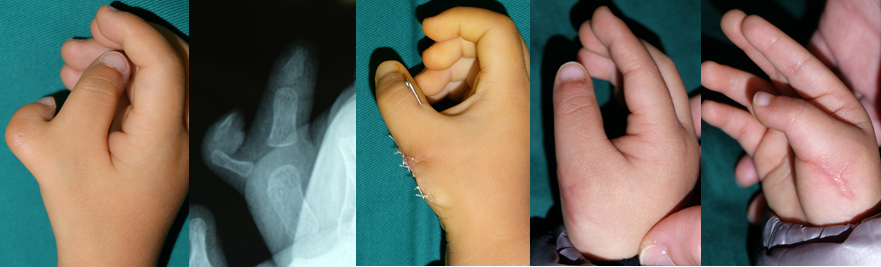

右拇指多指病例1例-医联

图片尺寸532x397